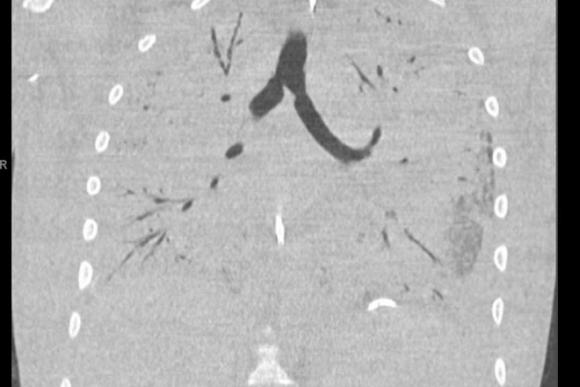

Phổi bệnh nhân bị sẹo, cứng, mục ruỗng với những điểm chết và viêm nặng. Ảnh chụp CT trước khi phẫu thuật cho thấy ngực cậu bé gần như trống rỗng, cả hai lá phổi cứ như đã biến mất khỏi đó.

Thông thường, những lá phổi của người khỏe mạnh sẽ tối đi trên phim vì chúng lấp đầy không khí. Phổi của bệnh nhân này không thể nhìn thấy vì chúng không làm việc. Không có chút không khí nào trong lá phổi.

Bác sĩ Nemeh và phim chụp phổi của bệnh nhân 17 tuổi bị ruỗng phổi do hút thuốc lá điện tử.

Bệnh nhân lẽ ra đã chết nếu không được ghép phổi mới, bác sĩ Nemeh nói. Phổi của cậu bé trắng xóa trên phim cho thấy nó đã bị viêm nặng, mục ruỗng với những phần chết không thể phục hồi.